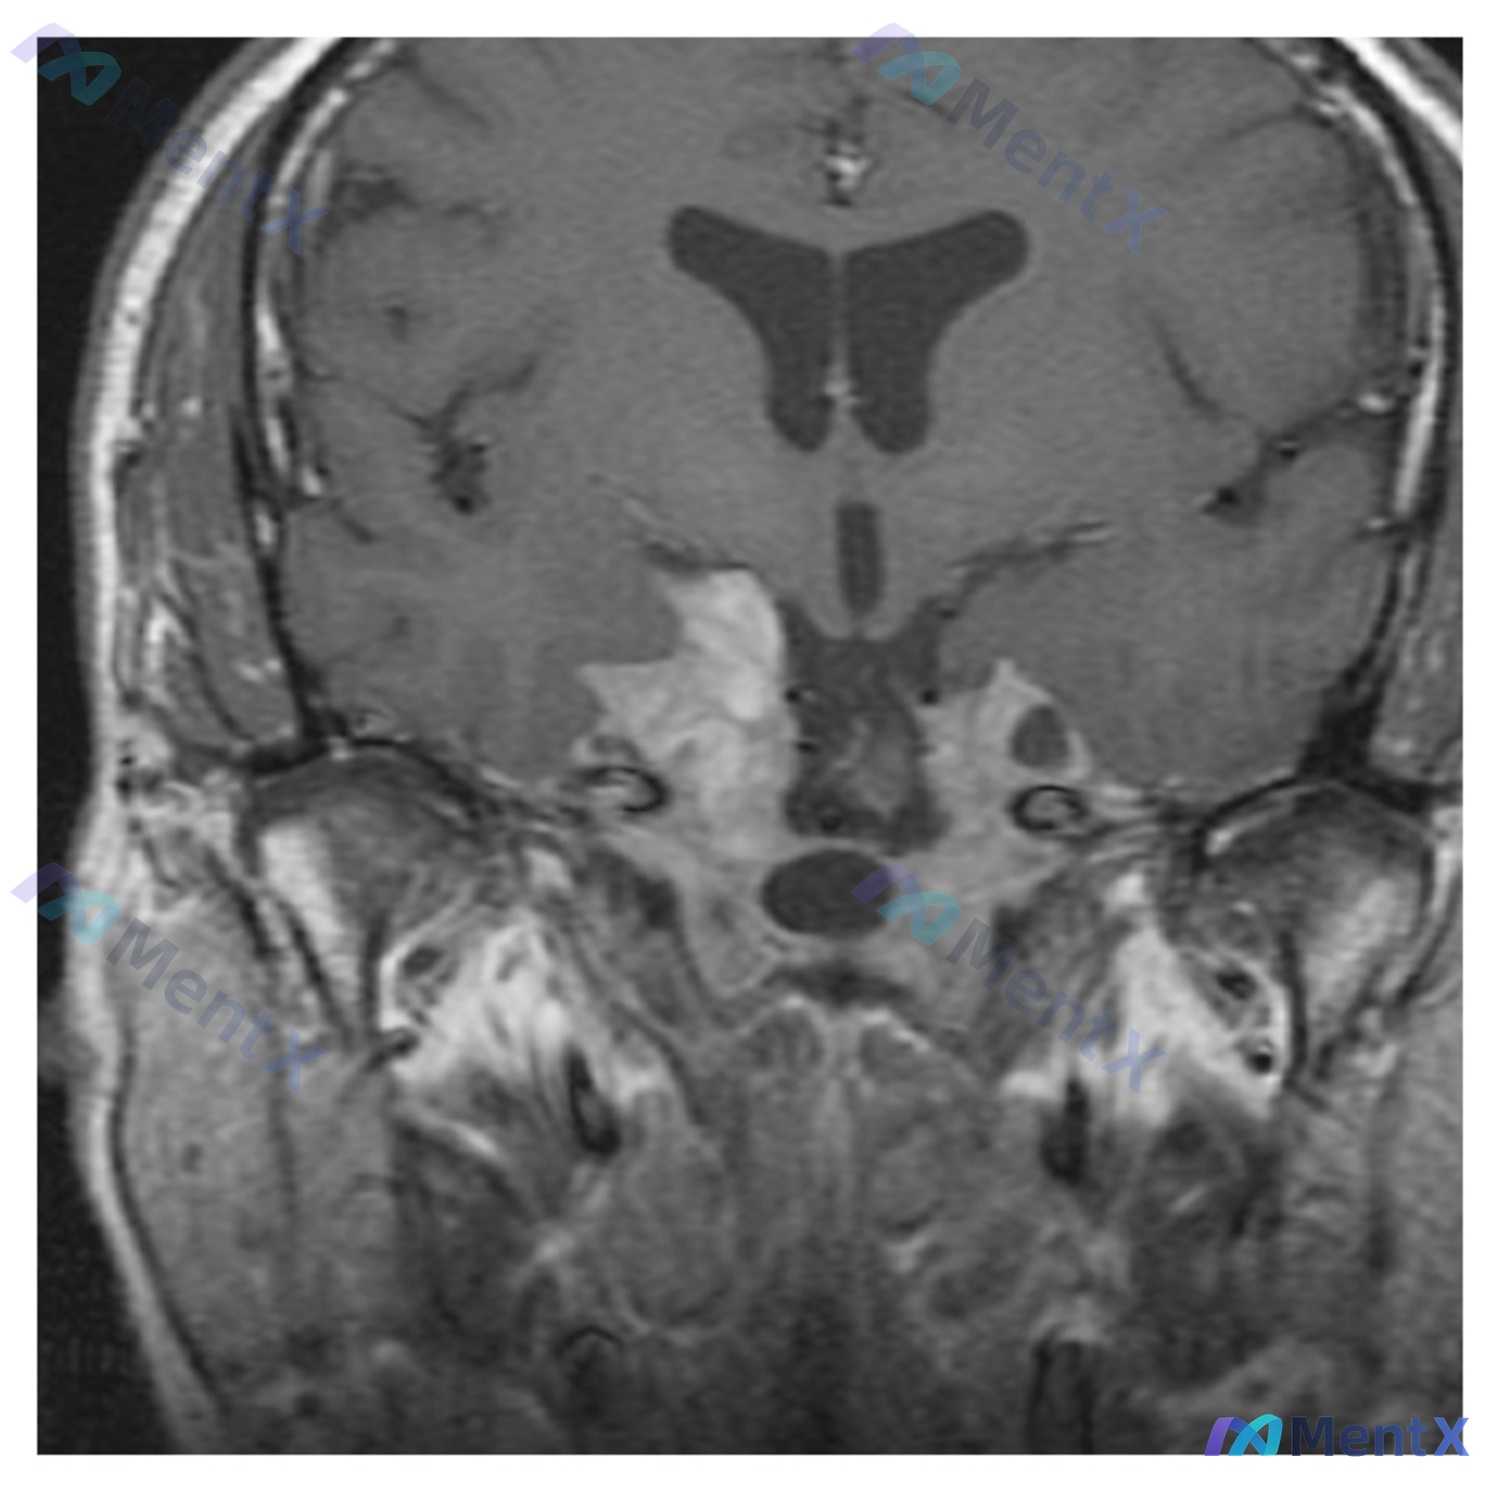

- 影像:脑部MRI冠状位(T1加权)

这张片子的异常还是比较明确的:

- 定位:病灶位于鞍区及鞍上池,向上摸到下丘脑/第三脑室底,向两侧侵及海绵窦

- 形态:不规则分叶状,鞍旁边界还可以,但和脑实质接触的地方有浸润感

- 信号:T1上是明显的混杂信号,有低信号的液性区(囊变/坏死),也有偏高信号的实性成分

- 占位效应:推挤视交叉和第三脑室,周围脑脊液间隙受压